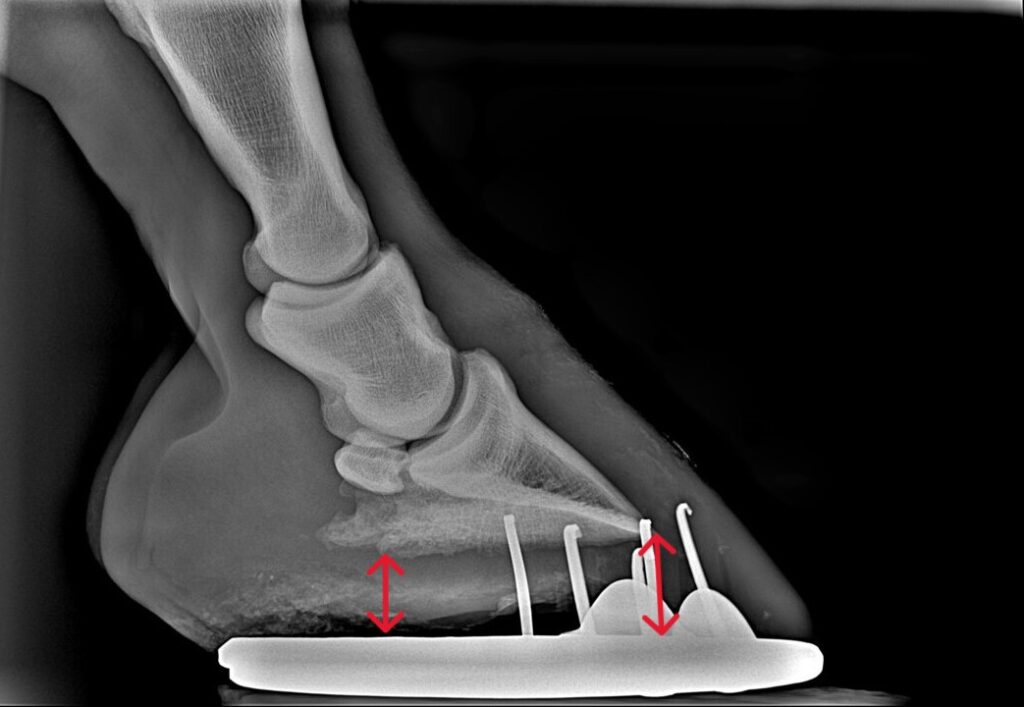

- Negative palmar foot angle is relatively common in warmbloods. The pedal bone, or PIII, is the bone inside a horse’s hoof. It is generally thought that the bottom surface of this bone should be at two to seven degrees relative to the ground surface. This creates a slightly toe downward angle and provides the horse with optimal balance and push off the feet, especially the hind legs. Horses with flat to negative palmar foot angles have a PIII bone that is elevated at the cranial edge (toe) and lower at the caudal edge (heel). These horses are essentially standing and moving from a “rocked-back” position, which places additional stress on the hind leg (high suspensory ligaments, hamstrings and gluteal muscles) and on the SI joint area.